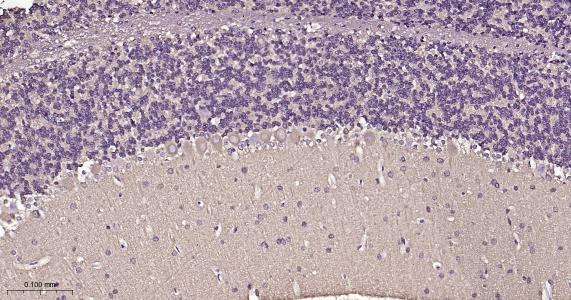

| IHC-P | Human, Mouse, Rat | 1:100-500 | |